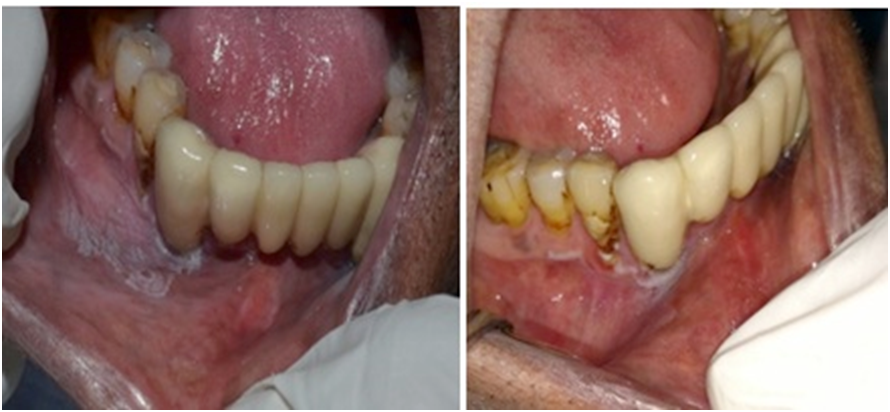

Smokeless tobacco-associated lesions were observed unilaterally in 69.0% and bilaterally in 21.0% of the participants. Eighty-four percent of cases were seen in the mandibular arch. The highest prevalence of cases was observed on the buccal mucosa, at 88.5%. A single case was reported in the retromolar mucosa, and no cases were identified on the tongue, floor of the mouth, or palatal region. Most of the lesions were present in the left mandibular vestibule (incisor and premolar region). The majority of the lesions were less than 3 cm in size (86.0%). The color of the lesion was white or grayish-white in 84.5% of cases, mixed red and grayish-white in 13.0%, and red in 2.6% of the study sample. The majority of the lesions (88.5%) had ill-defined margins. A total of 36.0% of the grayish-white lesions were scrapable. The lesion could be removed by pulling from the margin of the lesion, leaving an underlying erosive area. A plaque-like appearance was observed in 49.0% of cases, while 11.0% of the lesions showed a corrugated appearance. Tobacco-associated staining was observed adjacent to the dentition in approx. 68.0% of the lesions, and mucosal staining was seen in 34.0% of the lesions. Erythematous changes were present in 15.0% of the cases (Table 9). According to the classification proposed by Greer and Poulson, 59.1% of the participants demonstrated degree 1, 27.9% exhibited degree 2, and 13.0% displayed degree 3 of the lesions (Figure 2). Additionally, hard tissue changes manifesting as brownish discoloration were observed in the adjacent dentition due to the contact with the ST.

A total of 30 participants were randomly selected and followed for 6 weeks to observe the effects of quitting the adverse habit. Seven patients were lost to follow-up. The follow-up of the remaining 23 participants demonstrated that in 14 lesions, the clinical severity decreased following a reduction in the habit. Additionally, 7 cases showed complete resolution of the lesions, while 2 cases demonstrated persistence of white lesions at the lesion site even after quitting the habit for 6 weeks (Figure 4,Figure 5).

Previously, there has been a discrepancy in the terminology used for the classification of ST-associated lesions, as evidenced in studies by Axéll et al., Greer and Poulson, and Tomar and Winn (Table 11).10, 22, 24, 25 These classifications did not mention clinically scrapable features or loose tags of white lesions. Johnson et al. classified quid-induced localized lesions, irrespective of the presence or absence of tobacco in the quid.26 These lesions were considered to be equivalent to snuff-induced lesions at the mucosal contact site.26 Our clinical findings showed the presence of 36.0% of scrapable lesions in degree 2 and 3 lesions, regardless of whether the patient habitually used quid (Figure 7). As there is no uniform definition and terminology for lesions associated with tobacco and quid, we propose a uniform terminology and definition for ST-associated lesions, with the aim of facilitating communication among clinicians (Table 12). Our findings also revealed that a few lesions presented as ST-associated white non-scrapable lesions persisted even after habit cessation and could possibly represent the progression of the lesion to leukoplakia. These persistent white lesions could be diagnosed at the initial visit or after observing their persistence following the cessation of the habit for 6 weeks. A definitive clinical diagnosis of leukoplakia was considered when a negative result was obtained, even after the elimination of suspected etiologic factors, e.g., mechanical irritation, during a follow-up period of 6 weeks.27 Leukoplakia is a classic precursor lesion of oral cancer.28 Such lesions should be managed properly to prevent further severe dysplastic changes.